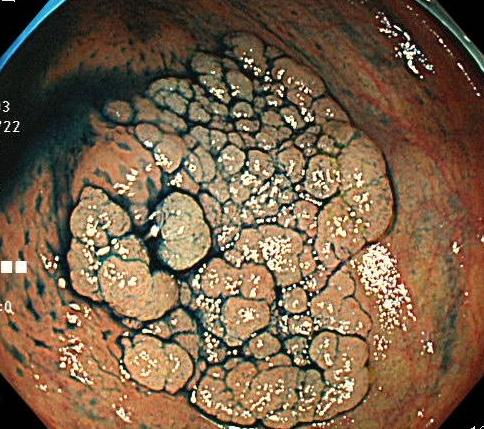

症例3:

<60歳代前半 女性 早期大腸がん>

部分義歯を飲み込み、レントゲン検査にて大腸内にとどまっているということで

大腸カメラ目的に当院を受診。

はじめて大腸カメラを受けました。

写真のような病変を認め、日帰り内視鏡治療を行い、こちらも「粘膜内がん」でした。

こちらの病変は「陥凹型」という珍しい病変でした。比較的小さいうちに進行していくため

気を付けないといけない病変でした。

偶然発見されて、患者さんも喜んでいました。結局、義歯は見つかりませんでした。